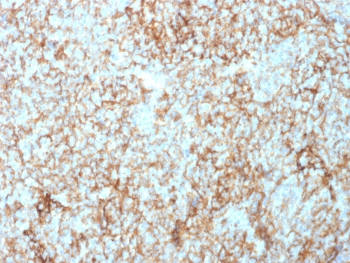

IHC staining of FFPE human tonsil tissue with CD73 antibody (clone NT5E/2545). HIER: boil tissue sections in pH9 10mM Tris with 1mM EDTA for 10-20 min and allow to cool before testing.

IHC staining of FFPE human tonsil tissue with CD73 antibody (clone NT5E/2545). HIER: boil tissue sections in pH9 10mM Tris with 1mM EDTA for 10-20 min and allow to cool before testing.